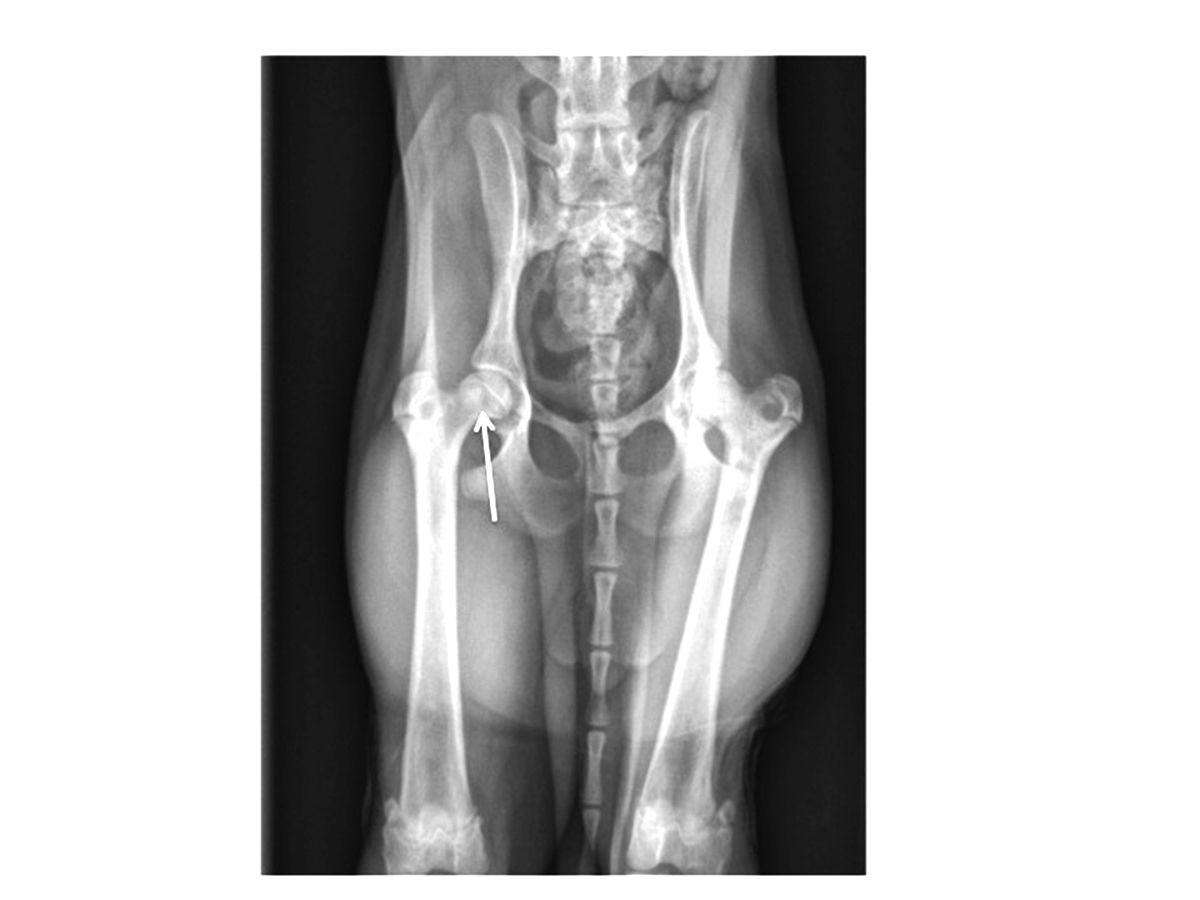

Même si l’examen clinique et l’anamnèse évoquent fortement une MLPC, des radiographies sont généralement réalisées pour confirmer le diagnostic. Initialement, des zones de lyse et de déminéralisation peuvent être présentes en région sous-chondrale de la tête et du col du fémur (Figure 1). La maladie progressant, un tassement franc de la tête et du col peut s’observer (Figure 2). Dans les stades plus avancés, des signes de reminéralisation et de cicatrisation osseuse peuvent être présents. Des anomalies arthrosiques secondaires peuvent s’observer, incluant la formation d’ostéophytes (notamment sur le pourtour acétabulaire dorsal et la tête fémorale) et l’aplatissement de la tête fémorale.

Cette radiographie met en évidence des anomalies modérées liées à la MLPC. La flèche montre une perte significative de la densité osseuse sous-chondrale au niveau du col du fémur, avec remodelage de la tête fémorale.

Figure 2. Cette radiographie met en évidence des anomalies modérées liées à la MLPC. La flèche montre une perte significative de la densité osseuse sous-chondrale au niveau du col du fémur, avec remodelage de la tête fémorale.© Darryl L. Millis